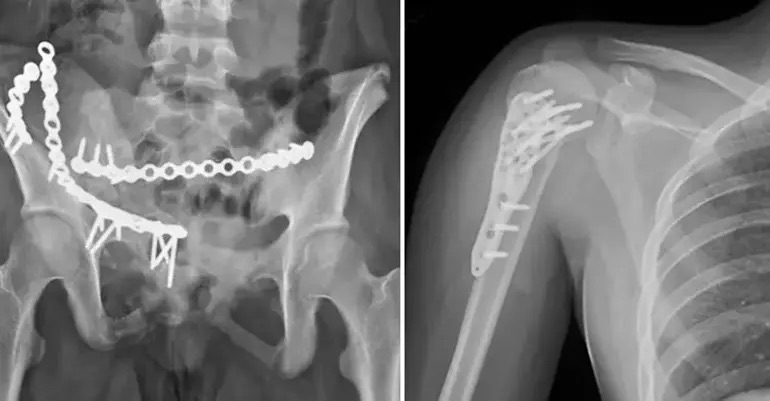

Survivor 2019 yarışmacısı milli güreşçi Okay Köksal’ın 15 yaşındaki kızı Azra, geçtiğimiz aralık ayında 8. kattan düşerek yaralanmıştı. Köksal, kızının sağlık durumu ile gelişmeleri sosyal medya hesabından paylaştı.